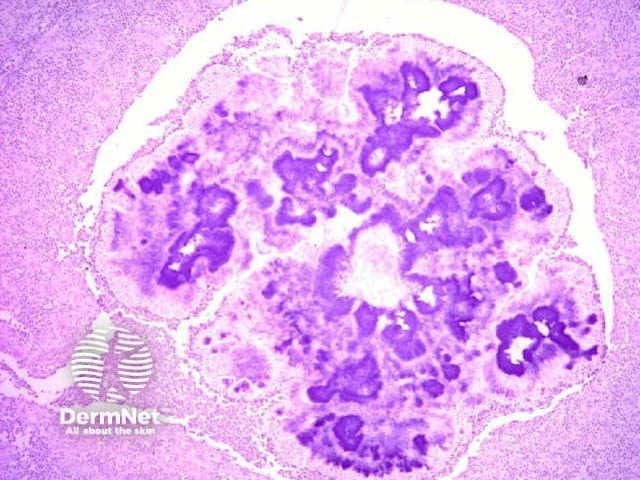

Skin biopsy may show typical histopathological features of mycetoma.

H&E stain of actinomycosis grains